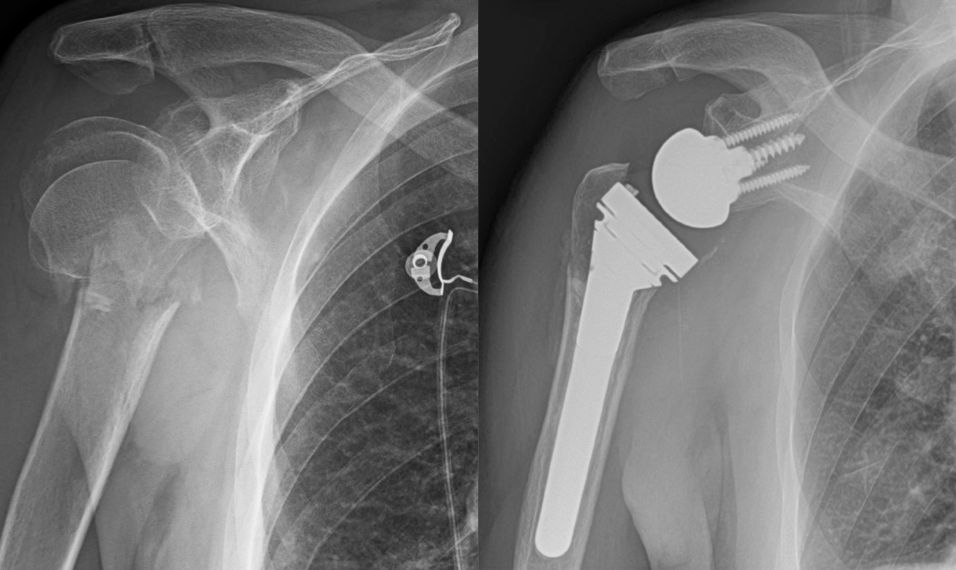

Proximal humerus fractures can involve four sections of the proximal humerus – the shaft, the ball, the lesser tuberosity, and greater tuberosity. Treatment options include non-operative treatment, surgical fixation, and replacement. The vast majority can be successfully treated without surgery. Depending on age, fragment displacement and angulation, some patients have better outcomes with surgical repair or replacement.

Shoulder radiographs demonstrating a complex proximal humerus fracture on the left, treated with a reverse shoulder arthroplasty on the right.